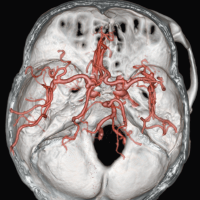

Клинические изображения

Компьютерный томограф Supria создан и производится в Японии фирмой Fujifilm.

Supria 32 рассчитан на сканирование всего тела с реконструкцией 32 срезов по данным, собранным за 1 оборот.